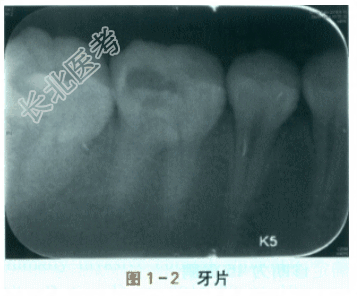

患者,女性,21岁,近3个月来,右下后牙咀嚼时经常出现疼痛,有时疼痛较重,换到左侧咀嚼疼痛就会缓解。平时吃冷热食物时,右下后牙也会感到疼痛。否认牙齿有自发痛病史,否认牙齿有夜间痛病史。既往史:否认牙病诊疗史,否认系统性疾病史,否认药物过敏史。查体:46面远中窝可见大而深的龋洞,内有食物残渣,去除食物残渣后可见大量的灰黑和黄褐色的龋坏组织(见图1-1),质软,轻用力可挑起部分龋坏组织,有轻度探痛。面近中窝可见小而浅的龋洞,色黑,探诊质地硬。颊面点隙可见黑色的点状龋洞,较浅,质硬,无探痛。颊颈部龈缘可见条带状浅黄色的菌斑,附着龈呈粉红色,边缘龈呈暗红色,无肿胀,探诊深度约2mm,无探诊出血。叩诊无疼痛,咀嚼棉卷无疼痛。冰条冷试验中度疼痛,无延迟痛。44、45、47未及明显龋损,牙周情况可。辅助检查:牙片检查发现46面远中可见透射影像近髓,根尖未见低密度影(见图1-2)。